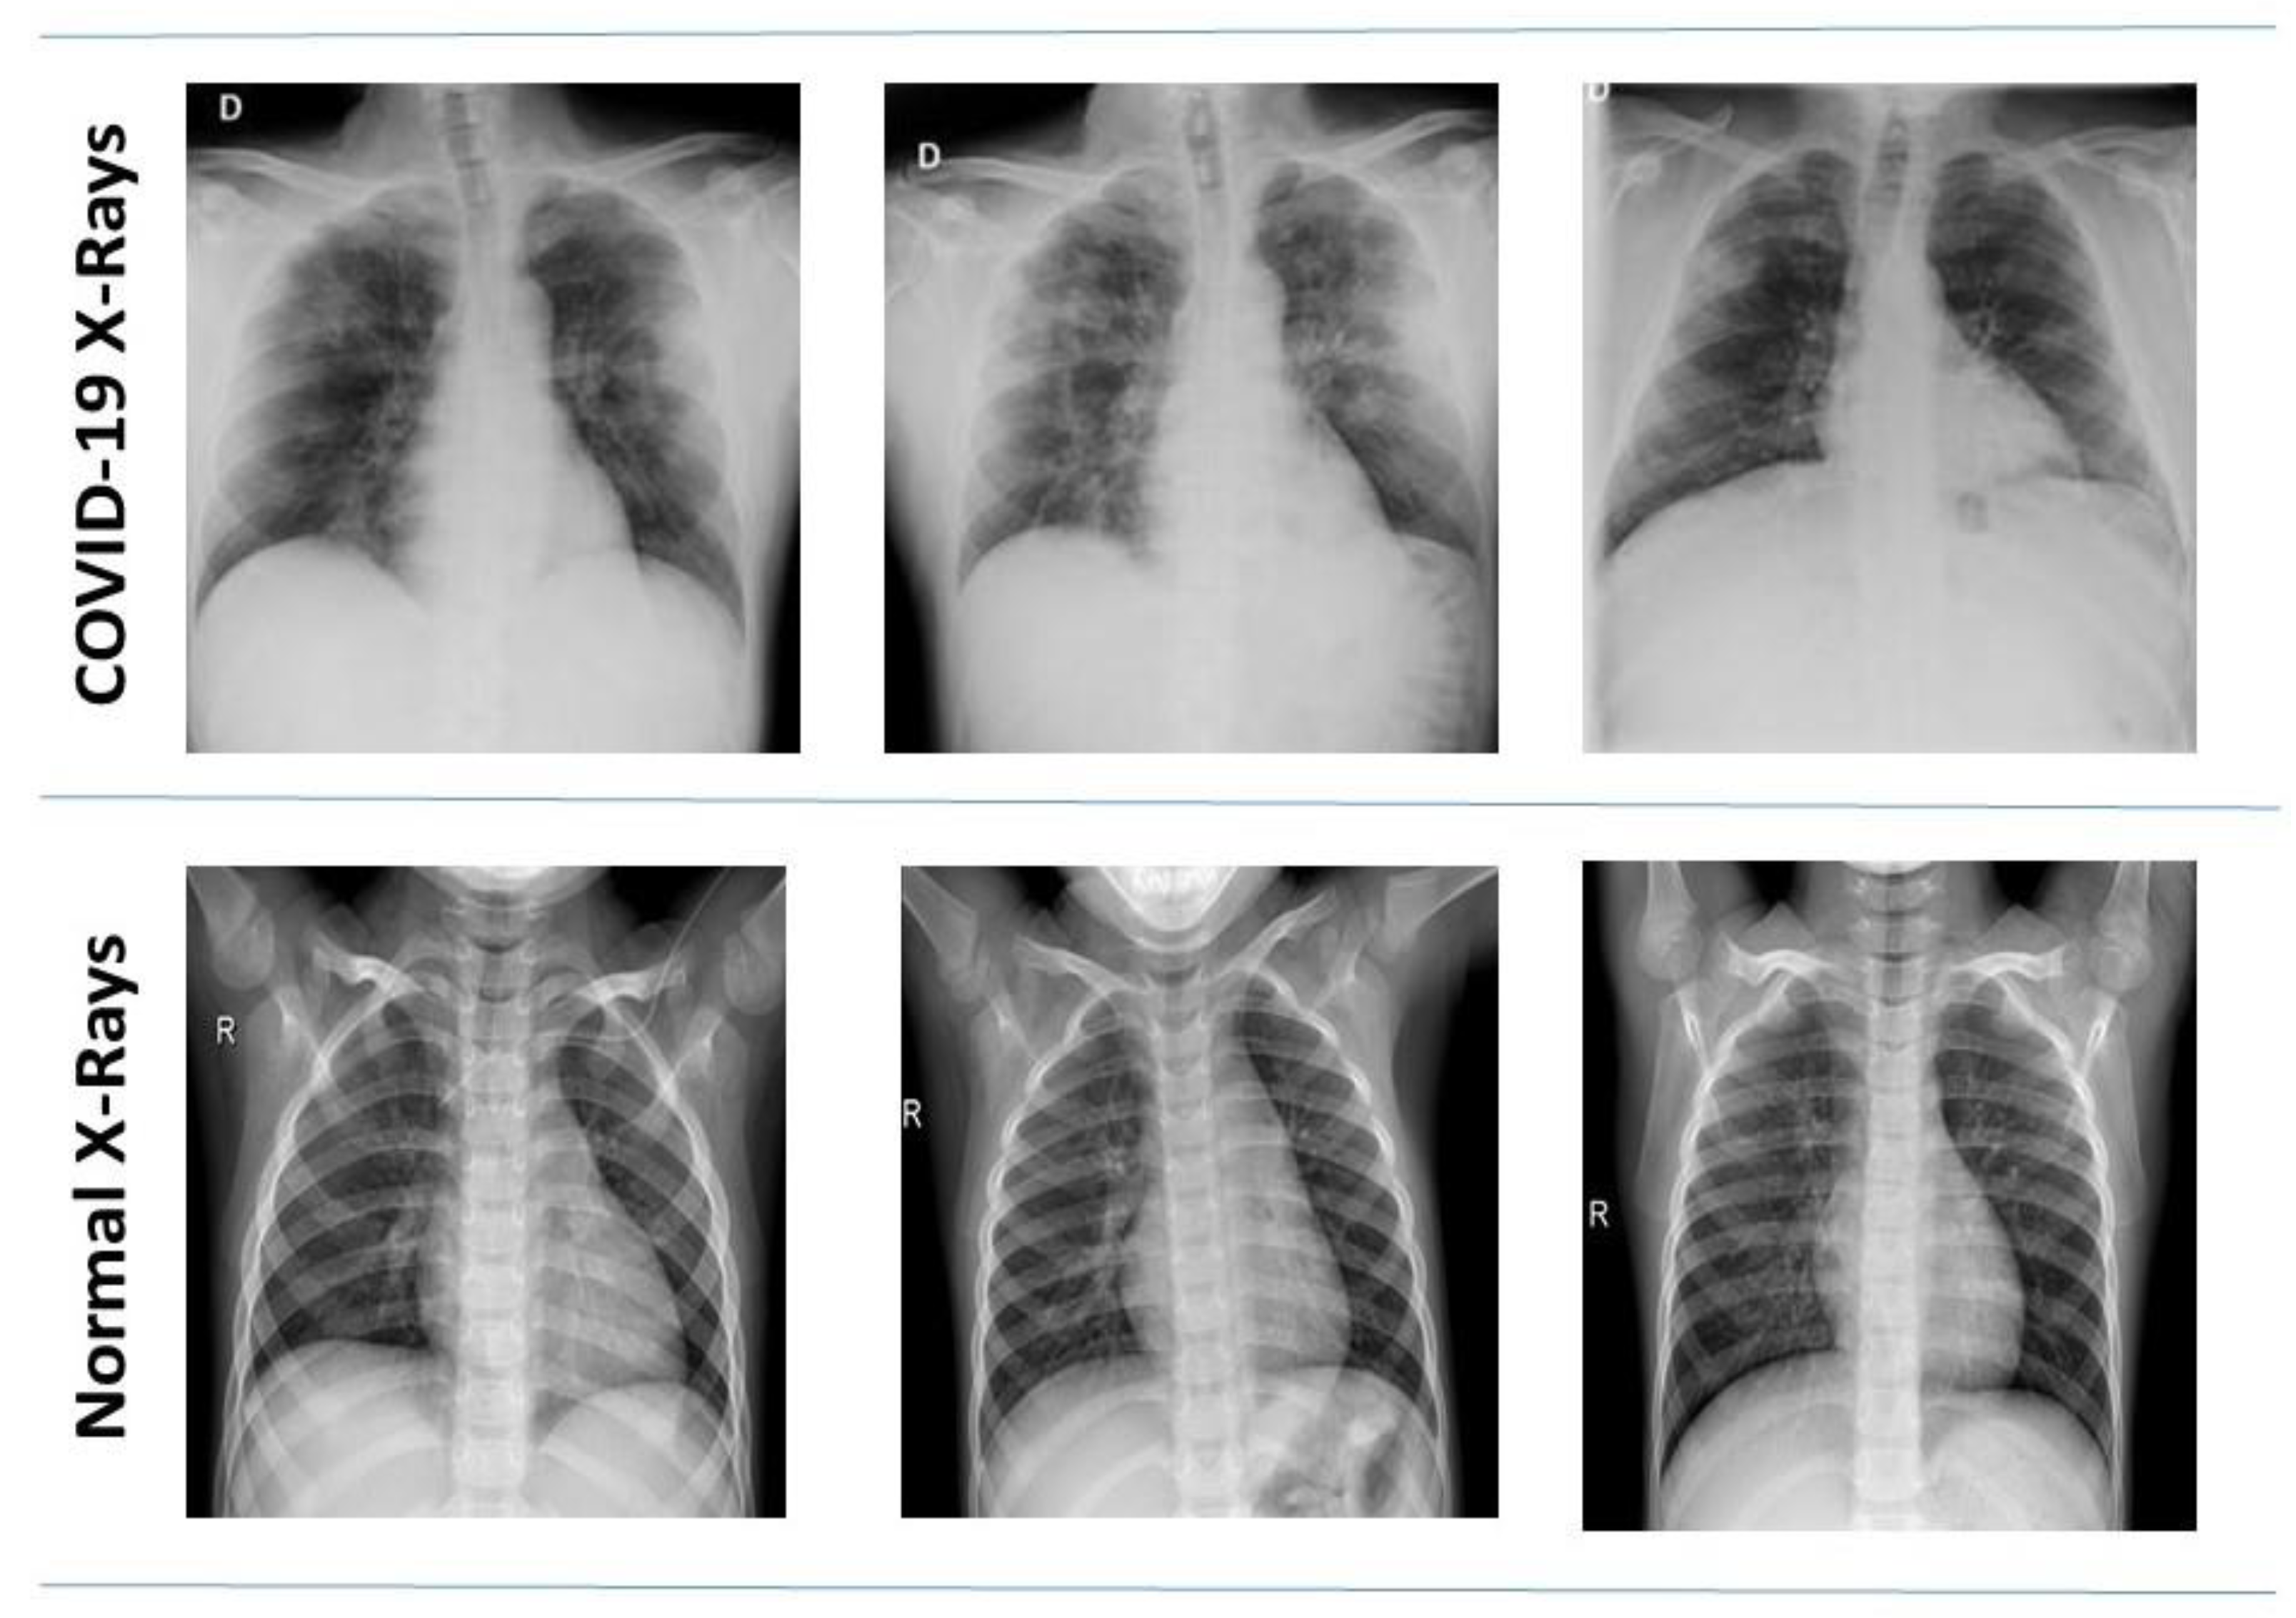

3.1.1. Kaggle COVID-19 Radiography Database

3.1.2. COVID-19 Chest X-ray Dataset by Joseph Paul Cohen

3.1.3. Data Distribution